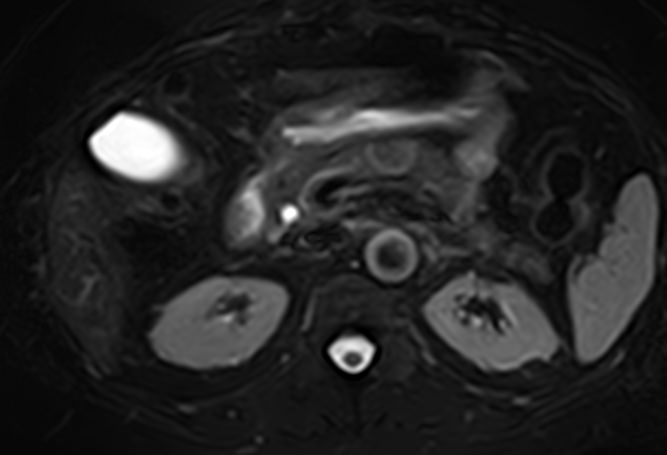

- камни в желчевыводящих протоках (холедохолитиаз) и желчном пузыре

- желчнокаменная болезнь

- калькулезный холецистит

Исследование желчных протоков и пузыря методом МРТ помогает объективно оценить состояние билиарного тракта и выявить патологические изменения на ранних этапах развития. Исследование проводят при подозрении на инфекционный, воспалительный или опухолевый процесс, а также для исключения конкрементов. МР-диагностика позволяет определить локализацию и характер патологических изменений и установить окончательный диагноз.